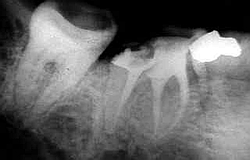

Bilder: Nur auf dem Röntgenbild ist der Störenfried zu erkennen

der Zahn will rauswachsen Durch den Druck schmerzt es sehr

Retinierte oder verlagerte Weisheitszähne haben keinen Platz im Kiefer. Beim aussichtslosen Versuch trotzdem herauszukommen, können Sie Nachbarzähne auflösen und schädigen oder das "das Gebiss verschieben. "Sie können auch Schmerzschübe auslösen . Deshalb sollten Sie besser entfernt werden. Wie bei jeder Operation muss vorher über mögliche Risiken wie Nervausfälle, Verletzung der Kieferhöhle und die Gefahr der Nachblutung aufgeklärt werden, selbst wenn die Wahrscheinlichkeit sehr gering erscheint. Die Risiken werden den voraussichtlichen Schäden durch den Verbleib des Weisheitszahnes gegenübergestellt. Erst nach Aufklärung und Einwilligung durch den Patienten wird der Eingriff durchgeführt. Bereits durchgebrochene Weisheitszähne sind oft schadhaft, da der Patient sie zum Putzen mit der Bürste fast nicht erreichen kann. Bevor sie als "Schmutzreservoir" auch den Nachbarzahn mit Karies anstecken sollte man sie besser ziehen. In diesem Fall verläuft die Extraktion einfacher mit weniger Risiken. Verhalten nach einer Operation. Manchmal ist der Zahn schon vorher inifziert oder entzündet sich nach der OP durch die Mundbakterien in diesem Fall muss die Naht wieder geöffnet werden und ein Medikamentenstreifen zum Ablass von Sekret und Eiter eingebracht werden.